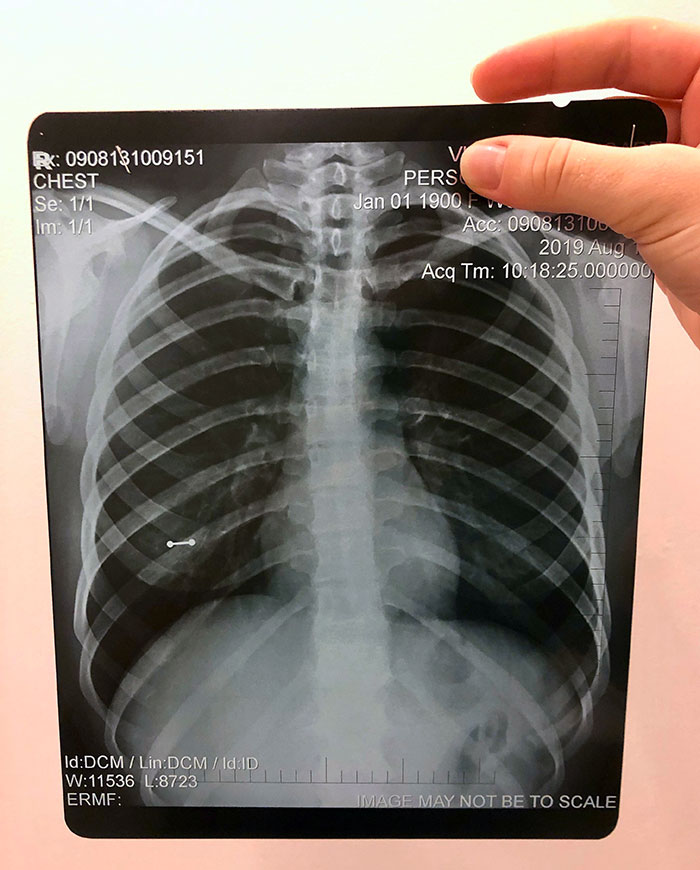

I Took This X-Ray On A Covid+ Patient Hours After My Friend Tried To Tell Me Covid Isn't That Bad

5-Day Progression Of Covid Pneumonia

General practitioner, medical researcher, and founder of PrimeHealth Clinical Research, Iris Gorfinkel, M.D., told Bored Panda that probably the most common X-ray of all is the chest X-ray, simply because it's often done when people are coughing, especially longer than a couple of weeks. "Other common X-rays that are fairly routine are mammography (looking for breast cancer in women) and CAT scans (we'll do CAT scans of the chest, the abdomen, and that's often to look for various cancers as well)."